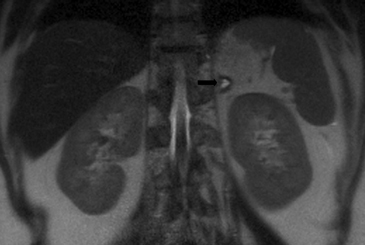

En la TC no contrastada las glándulas suprarrenales normales son homogéneas y simétricas, con una densidad muy similar a la del parénquima renal adyacente (Figura 1 a). Con un medio de contraste ev la glándula suprarrenal se opacifica en forma homogénea, similar al hígado o al bazo (Figura 1 b). Si la cantidad de tejido adiposo retroperitoneal es abundante las glándulas suprarrenales pueden aparecer enteramente rodeadas por grasa y su delimitación es más fácil (Figura 2 a); lo inverso ocurre en pacientes muy delgados con escasa grasa retroperitoneal (Figura 2 b). En RM, en secuencias ponderadas en T1 y T2 convencionales tienen una intensidad de señal homogénea, hipointensa respecto de la grasa adyacente e iso o hipointensa con respecto del parénquima hepático (Figura 3 a y b). En los cortes coronales se aprecia mejor la forma y la posición de las glándulas suprarrenales (Figura 3 c).

Figura 3. Glándula suprarrenal normal en resonancia magnética. (a) Cortes axial ponderado en T1 la señal de la glándula normal (flecha negra) es hipointensa respecto a la grasa retroperitoneal e isointensa respecto al parénquima hepático. (b) Cortes axial ponderado en T2 en que se muestra la glándula suprarrenal derecha (flecha blanca) y (c) corte coronal ponderado en T2 en que se muestra la glándula suprarrenal derecha (flecha blanca) y la glándula suprarrenal izquierda (flecha negra) con similares características de intendidad de señal. 3. Causas y prevalencia de las lesiones suprarrenales